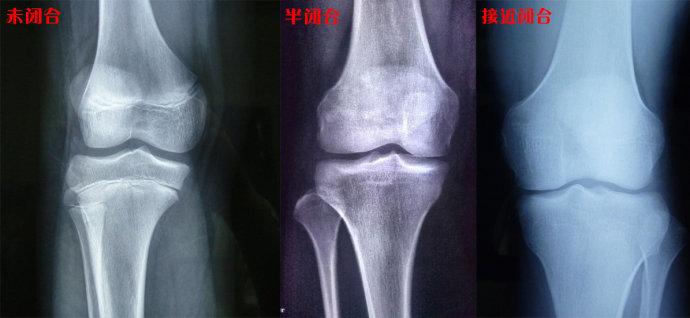

骨骺线闭没闭合对比图

图片尺寸1080x1439